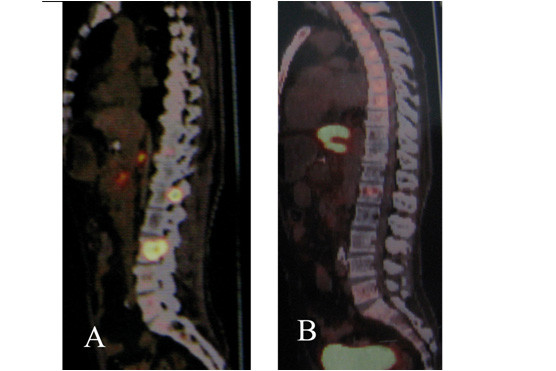

4、脊髓血管畸形、脊柱、椎管内和脊髓肿瘤的射波刀治疗: 脊髓血管畸形主要引起出血、盗血、脊髓压迫和静脉压增高症状,目前的主要治疗方法有介入治疗、显微外科治疗和介入-显微手术联合治疗。射波刀的出现为脊髓血管畸形提供了另一种治疗选择。Sinclair 等人最近报道了射波刀治疗15例脊髓血管畸形的初步结果。他们采用低分割照射(2~5次),经过2~5次的射波刀治疗,病灶周边的平均剂量为20.5Gy,平均随访时间为27个月。随访3年以上的患者中,脊髓血管畸形明显缩小,1例血管畸形经DSA证实完全消失。华山医院治疗1例颈段脊髓AVM,治疗后半年症状改善,治疗后1年走路跛行症状消失。椎管内脊髓外良性肿瘤也可选择射波刀治疗,但是当脊髓有受压症状时,最好选择手术治疗。椎管内小的多发神经纤维瘤是射波刀治疗的良好适应证,射波刀治疗后,多数肿瘤得到控制未再增大,1/3肿瘤缩小。椎管外的神经纤维瘤是射波刀治疗的良好适应症,治疗后肿瘤缩小(如图9所示)。脊髓内恶性肿瘤特别是一些转移瘤,除了引起脊髓受压症状外,还因神经根受刺激而产生疼痛症状;虽然常规放疗能在一定程度上起到控制肿瘤减轻疼痛的作用,但其治疗作用有限。射波刀的低分割照射对脊柱转移瘤和脊髓内转移瘤不仅可以起到控制肿瘤生长(或使肿瘤缩小),还可以明显减轻疼痛,改善患者的临床症状(如图10)。

图10:肝癌脊柱转移,患者疼痛症状明显。A: 射波刀治疗前,PET-CT显示腰1椎根和腰3锥体转移瘤; 射波治疗后一周,疼痛症状消失。B: 射波刀治疗后1月复查PET-CT显示转移瘤病灶的FDG(葡萄糖)摄取变为正常。